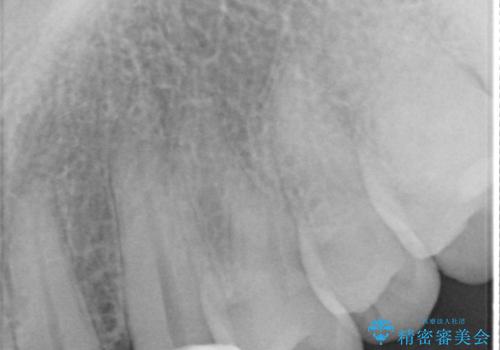

- 転んで欠けてしまった前歯を治したいと来院された患者様です。

この機会に、白くきれいにしたいとの事でした。

まず仮歯に置き換え、最終的な被せものの前に仮歯で形などを調整します。

その後精度の高いシリコーンによる型どりを行います。

歯の神経は生きていますが、精度の高い被せもののため冷たいものがしみるなどの症状もなく、きれいになったと満足していました。